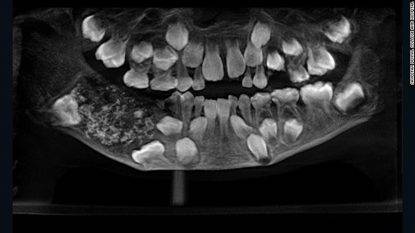

Il Dottore Senthilnathan, professore del dipartimento di chirurgia orale e maxillofacciale, ha spiegato che dopo la Tac è stata rilevata una “struttura a forma di borsa” che conteneva i denti: “La crescita simile a un tumore ha impedito la crescita permanente dei denti molari nel paziente nella parte interessata. La radiografia e la TAC hanno mostrato denti multipli e originari in un tessuto simile a una borsa”.

Il Dott. Ravindran ha riferito cosa hanno trovato nella bocca del piccolo: “Non abbiamo mai visto così tanti denti in nessun paziente. I denti avevano dimensioni diverse che variavano tra 0,1 mm e 15 mm. Sembravano perle in un’ostrica. Anche il pezzo più piccolo aveva una corona, una radice e un rivestimento di smalto come un dente”. L’intervento è stato effettuato con l’anestesia generale, che è stata completata in circa un’ora e mezza. Successivamente, i chirurghi hanno impiegato cinque ore per rimuovere i 526 denti dal “sacco“.